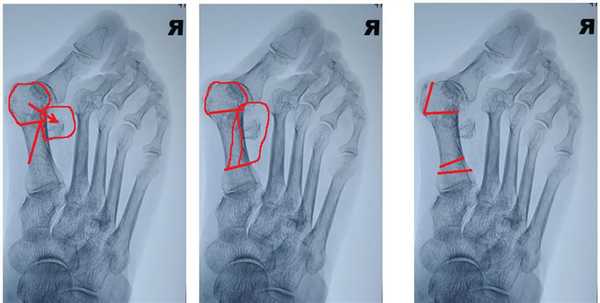

Инструментальные методы диагностики. Для подтверждения диагноза халлюкс вальгус и предоперационного планирования используются рентгенограммы в прямой, боковой, и иногда косой и сесамовидной проекциях. Основными параметрами которые оцениваются рентгенологически являются:

1. угол халлюкс вальгус (в норме менее 15°)

2. межплюсневый угол (в норме менее 9°)

3. Дистальный плюсневый суставной угол (в норме менее 15°)

4. Межфаланговый угол халлюкс вальгус - угол между проксимальными фалангами первого и второго пальцев (в норме менее 10°)

Рентгенологическое определение углов при вальгусной деформации первого пальца стопы.